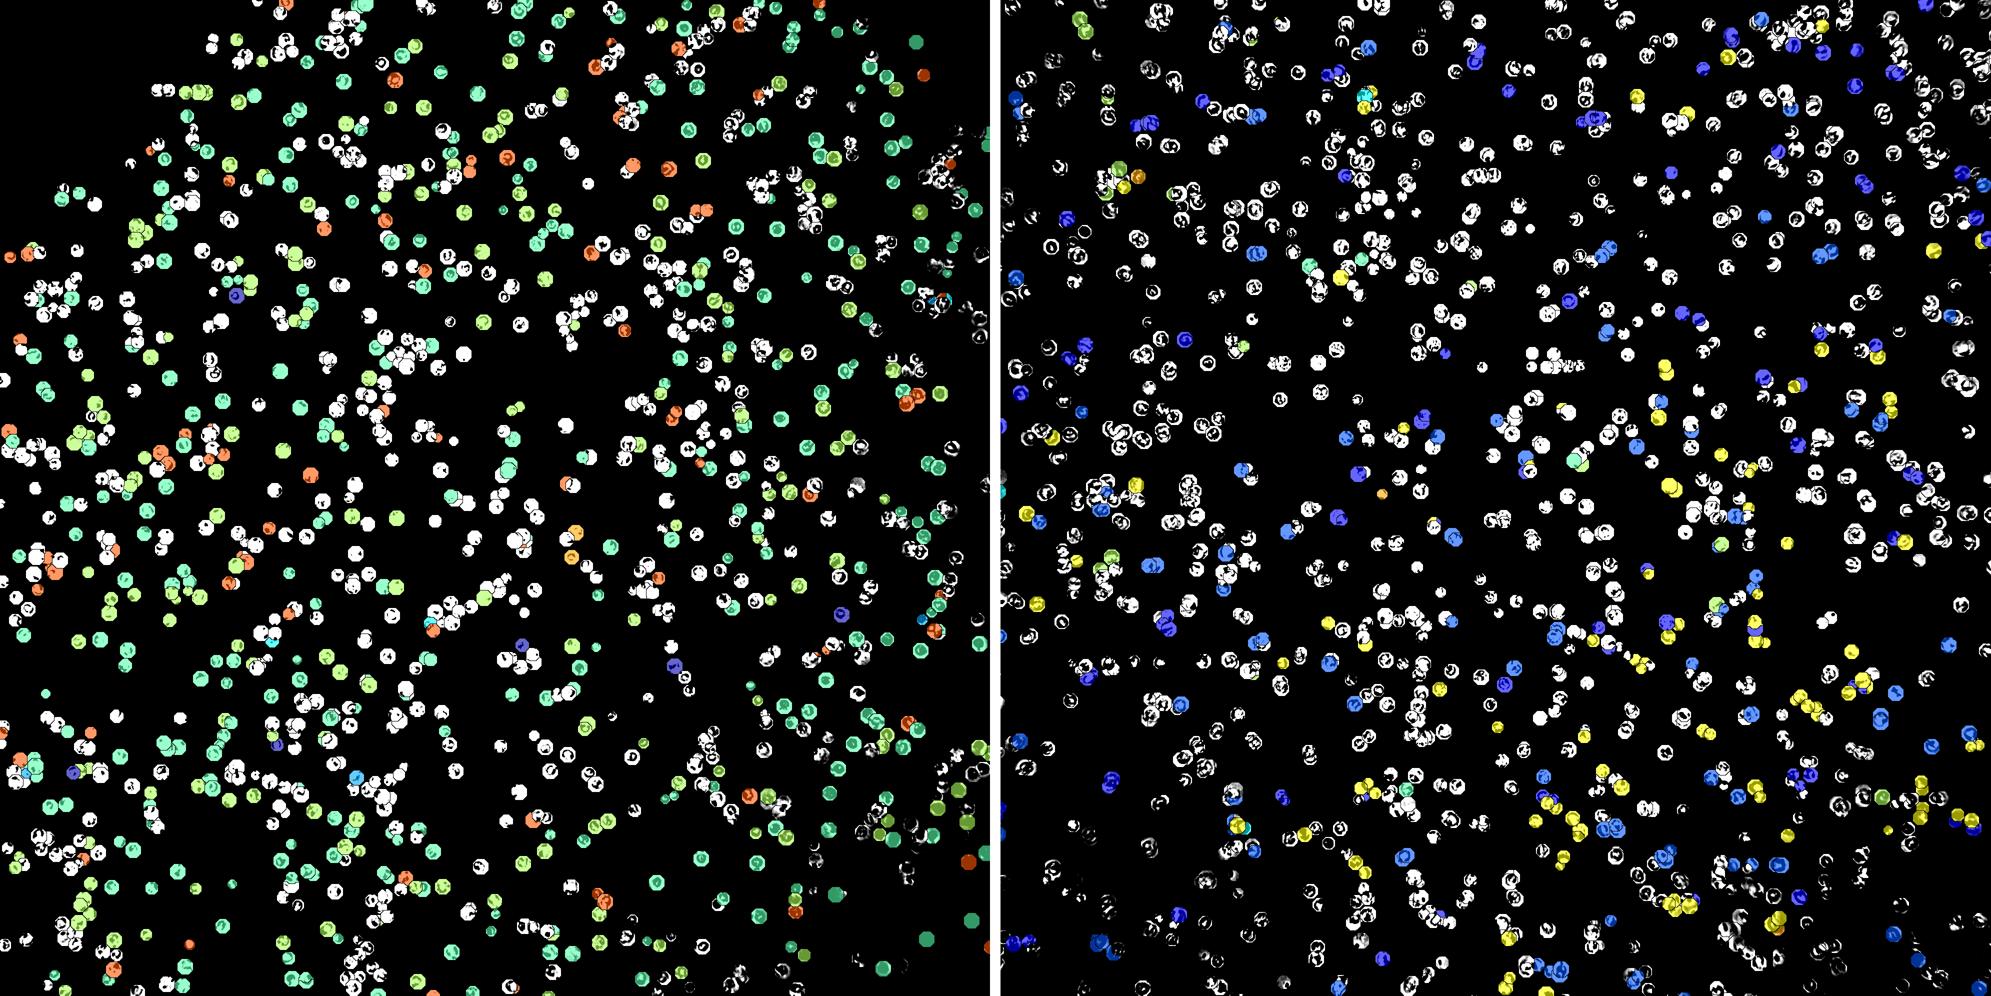

Cells labelled with CD24 CD8a

Peripheral blood lymphocytes

Inflammatory Disease

Cell populations before and after treatment